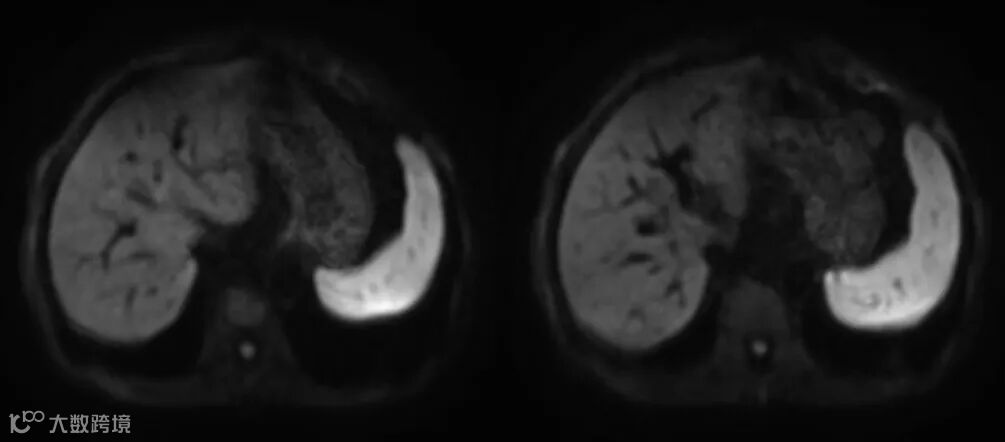

:位移像素数 = 水脂频差 / 像素带宽 - 扩散加权成像(DWI)

在实际临床扫描中对于一些特殊的成像序列通常使用高带宽才能更好抑制其磁敏感伪影,如稳态序列,平面回波DWI序列等。